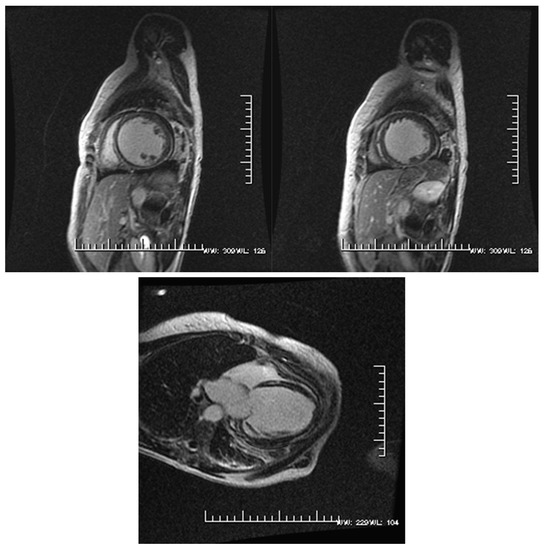

Can 3D RVEF be Prognostic for the Non-Ischemic Cardiomyopathy Patient but Not the Ischemic Cardiomyopathy Patient? A Cardiovascular MRI Study

:1. Introduction

2. Materials and Methods